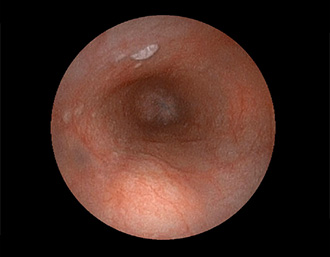

症例3:十二指腸潰瘍(53才男性)

1年前からの慢性胃痛を主訴に当院受診。十二指腸球部前壁に深くて大きな潰瘍(Stage A1)があり、潰瘍底は厚い白苔に覆われ、一部白苔のはみ出しを認める。潰瘍周囲粘膜は浮腫を伴っている。ボノプラザンフマル酸塩投薬で治療開始しました。

(通常画像)